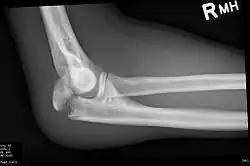

Olecranon fracture

Olecranon fracture is a fracture of the bony portion of the elbow. The injury is fairly common and often occurs following a fall or direct trauma to the elbow. The olecranon is the proximal extremity of the ulna which is articulated with the humerus bone and constitutes a part of the elbow articulation. Its location makes it vulnerable to direct trauma.

To assess an olecranon fracture, a careful skin exam is performed to ensure there is no open fracture. Then a complete neurological exam of the upper limb should be documented.[5][2] Frontal and lateral X-ray views of the elbow are typically done to investigate the possibility of an olecranon fracture.[1] A true lateral x-ray is essential to determine the fracture pattern, degree of displacement, comminution, and the degree of articular involvement.